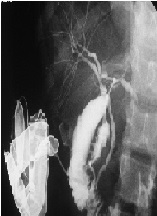

Intraparenchymal Stenting in Blunt Liver Trauma: A Case Report of a Simultaneous Damage-Control and Tissue-Sparing Surgical Technique

Edgar Fernando Hernández-García*, José Lauro Gilberto Delgado-Arámburo, Luis Manuel García-Núñez, Hector F Noyola Villalobos, Fernando Federico Arcaute-Velázquez